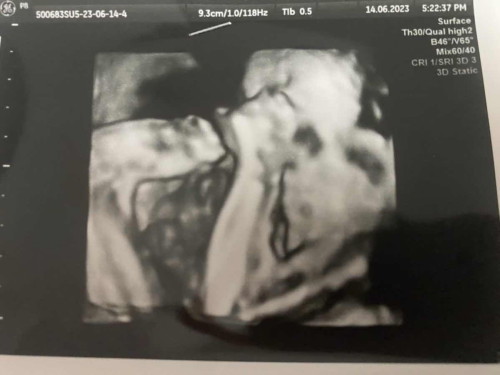

น้ำหนักลูกในครรภ์เท่าไหร่กันแล้วคะ ตอนนี้27w4d แม่น้ำหนักขึ้น3กิโล มีตัวช่วยสำหรับบำรุงให้ลูกน้ำหนักเยอะๆมั้ยคะ

บ้านนี้น้องพึ่ง นน.927 กรัมเองคะ แต่หมอบอกตามเกณฑ์